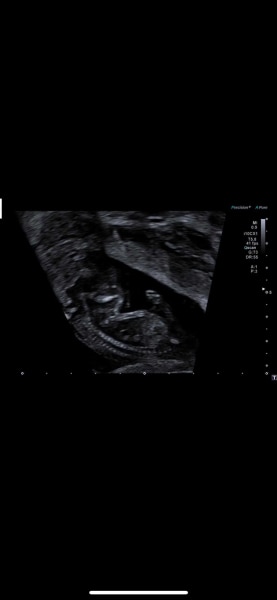

Hi, was vermutet ihr? Mädchen oder Junge? Eine Tendenz wurde von der Gyn heute abgegeben...

Bild zu Mädchen oder Junge? :-) - Schwanger - wer noch? Rund um die Schwangerschaft

Huhu Mrsr, ich hab deine Bilder gerade glaube ich Gefühl 20 mal angeguckt und bin neugierig, was du für eine Tendenz bekommen hast.  Meine Vermutung wäre ein Junge.  Beim ersten Bild steht es ein bisschen nach oben und auf dem Nub ist noch eine kleine Wölbung.  Das zweite Bild find ich persönlich schwierig zu beurteilen, weil das Baby dort ein bisschen zur Seite gedreht ist .Da ist der Nub gerader, was wiederum eher für ein Mädchen sprechen würde. Allerdings ist der Nub recht dick, was mich irritiert (könnte aber auch einfach dicker wirken, weil das Baby gedreht ist und man den Nub und oben drauf die Wölbung zusammen auf ein Bild bekommen hat 🙆‍♀️...  Für ein Mädchen Nub fehlt halt diese Typische Gabelung... je mehr ich schreibe merke ich dass ich immer mehr zum Baby Boy tendiere.  LG Cleo

ja uns wurde Junge gesagt....